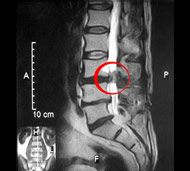

Чтобы определить, есть ли у вас межпозвонковая грыжа, врач соберет анамнез и проведет неврологическое обследование. В частности, он проверит симптомы, указывающие на сдавление нервных структур, а при их наличии исследует, насколько эти структуры потеряли свою функцию. Однако решающими в диагностике заболеваний позвоночника являются такие методы обследования, как:

- Магнитно-резонансная томография (МРТ). Для создания изображений вашего тела используется магнитное поле. Это исследование применяется для подтверждения локализации грыжи межпозвоночного диска и определения пораженных нервов. МРТ является золотым стандартом диагностики грыж межпозвонковых дисков.

![]()  |